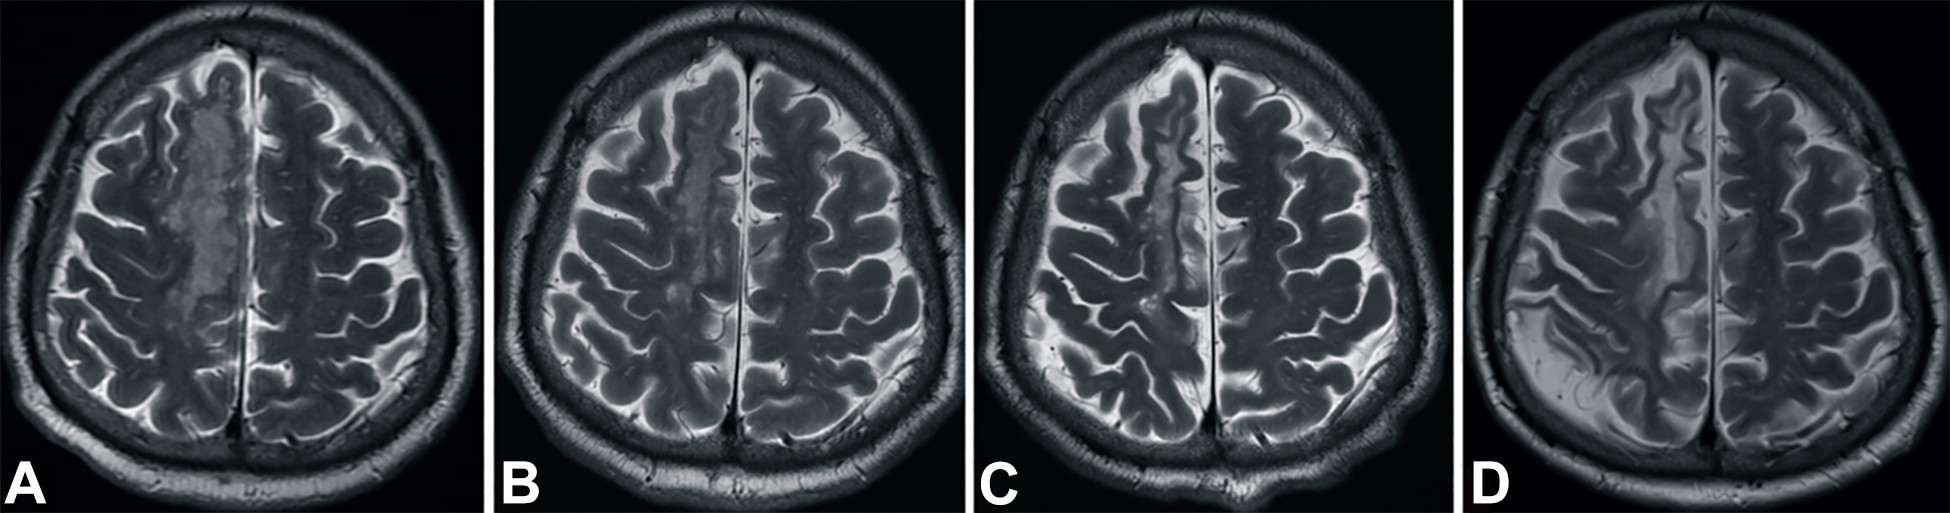

梗塞發(fā)生后2小時、8 天、3 個月和 6個月獲得的T2加權(quán)圖像顯示右側(cè)放射冠白色強度增加(圖3A-D)。